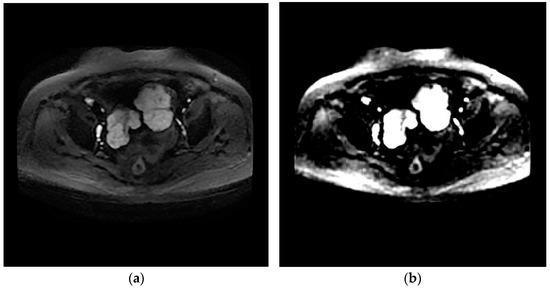

The design of the network can provide the value of image features. The network eliminates redundant information through learners and decoders, and only retains features that can reflect the inherent characteristics of HGSOC, and therefore a small number of features can contain most of the information of tumor images. Therefore, we input T2WI and DWI images from the same patient into the network and reconstructed them into images. It was found that the reconstructed images based on the features were similar to the original images, which proves that the internal features of the images are learned, as shown in Figure 3 and Figure 4.

Figure 4.

Axial DWI image (a); generated image (b).